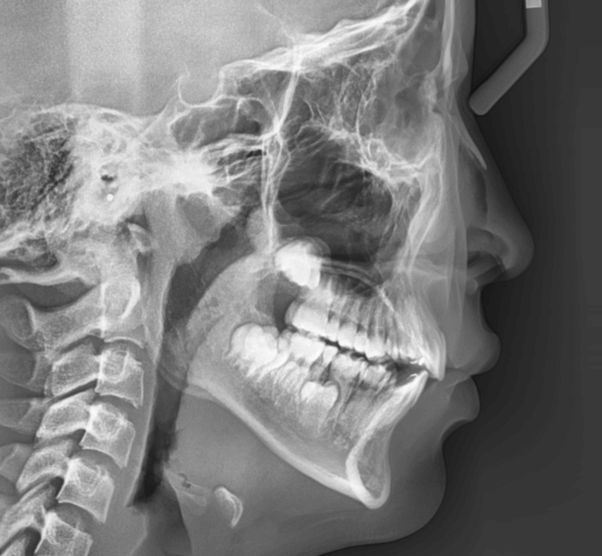

主訴 | 前歯の噛み合わせが逆で、見た目や食事に違和感があることを心配されて来院されました。 |

---|---|

診断結果 | 7歳8か月の男児 前歯の反対咬合診断 |

治療内容 |

|

治療後の経過 | 早期矯正治療は11歳5か月で終了し、現在は3〜4か月ごとの定期検診で経過観察中で、今後本格的な矯正治療へ移行予定です。 |

治療期間 | 3年6か月 |

治療費用 | 430,000円(税別) |